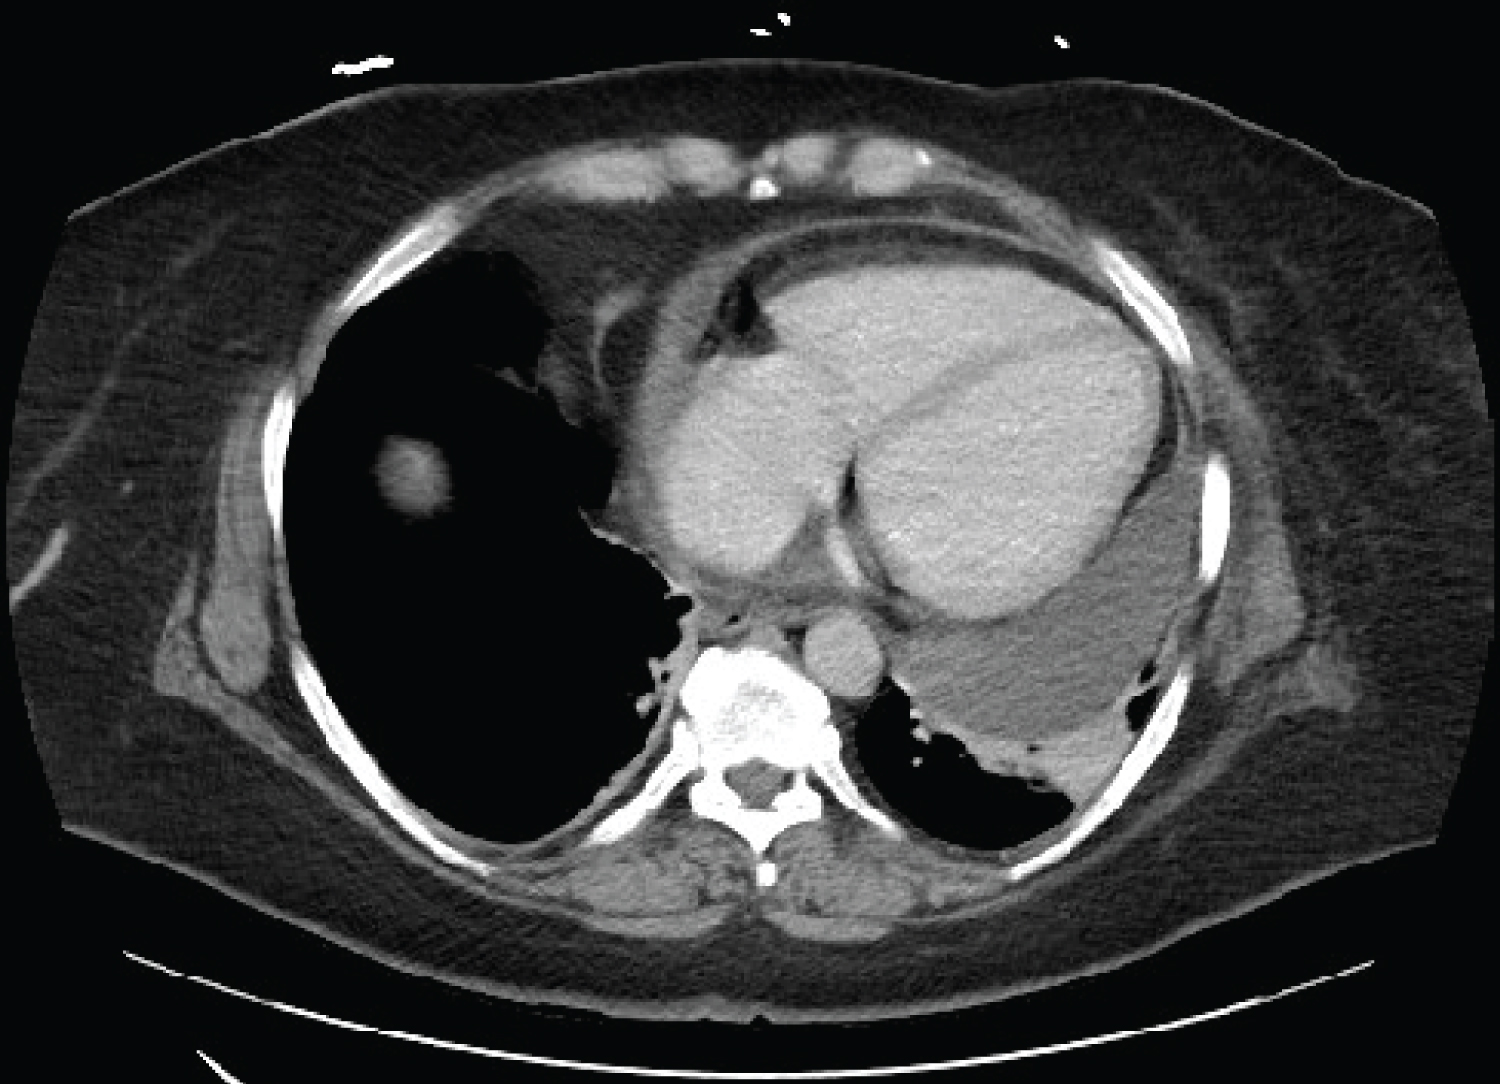

A 52-year-old female recently underwent symptomatic anterior diaphragmatic hernia repair due to majority of her stomach being found within her thoracic cavity at a nearby hospital. After evaluating the patient and imaging the surgeon preferred an abdominal approach compared to a thoracic approach because of his experience with the approach. The hernia repair required 0 silk suture placed in a figure eight fashion through the anterior diaphragm on each side of the hernia to the anterior abdominal wall. A Ventzio ST hernia (8 × 12) patch, an uncoated monofilament polypropylene mesh, was placed and it was fixed in place using the Ethicon secure strap in a double crown technique. Postoperatively patient developed lightheadedness and dizziness and was found to have a moderate pericardial effusion on transthoracic echocardiogram (TTE). Patient had a pericardiocentesis and 350-400 cc of dark brown pericardial fluid which was drained by vascular surgery team. The pericardial fluid analysis was nonspecific and the cultures were negative. She had reaccumulation of the pericardial fluid and a new left pleural effusion which required placement of a pericardial window. Patient presented to our emergency room three weeks later with palpitations, lightheadedness, and chest pain. She gave a past medical history of paroxysmal atrial fibrillation, hypothyroidism, depression, and gastroesophageal reflux disease. Her symptoms were similar to her previous hospitalization for pericardial effusion. Electrocardiogram (EKG) demonstrated atrial fibrillation with rapid ventricular rate. TTE and demonstrated moderate to large pericardial effusion. CT chest angiography demonstrated a large pericardial effusion (Figure 1). Patient was evaluated by both cardiothoracic surgery and vascular surgery due to recurrent pericardial effusion, she was not a candidate for reintervention due to the loculated posterior location of the effusion. Since this was a recurrent episode, within three weeks, it was recommended to transfer patient to a tertiary center for further evaluation. At the tertiary facility she was evaluated by a cardiothoracic surgeon who did not recommend any further intervention due to limited pericardial fluid to drain. Patient presented to the ER for shortness of breath and palpitations two weeks after being transferred from our facility. EKG demonstrated atrial fibrillation with rapid ventricular response. TTE demonstrated pericardial effusion and left sided pleural effusion. Patient required a diltiazem drip and was switched from home medication sotalol to flecainide to achieve rate control. Patient was reevaluated by vascular surgery who had no further recommendations on management. She was also evaluated by general surgery because her recurrent pericardial effusion started following her diaphragmatic hernia repair. It was determined that her recurrent pericardial effusion is due to reactive inflammation from tackers used to secure the mesh and it will improve as the inflammation resolves. Patient returned to the ER two weeks later complaining of chest pain, headache, and shortness of breath. Vitals were temperature: 98.2 F, blood pressure: 101/63 mmHg, heart rate: 117 beats per minute, respiratory rate: 24 breaths per minute, oxygen saturation: 97%. Patient appeared in no acute distress. EKG demonstrated atrial fibrillation with rapid ventricular rate. She was started on diltiazem drip and her flecainide was stopped due to side effects. Patient’s allergies to beta blocker and amiodarone made it challenging to achieve rate control. She converted to sinus rhythm with rate control and was switched from intravenous to oral diltiazem. Digoxin was added to maintain rate control. CT chest with contrast demonstrated a left sided pericardial effusion (Figure 2). Patient was evaluated by vascular surgery and general surgery again. They decided the patient would require a pericardial window and removal of the mesh if she continued to have recurrent pericardial effusions. Cardiothoracic surgery recommended that patient be evaluated at a larger facility for repeat pericardial window. Patient was transferred to a tertiary facility and was evaluated for a CT-guided pericardiocentesis. Due to improvement of her symptoms, the CT-guided percardiocentesis was not performed and she was discharged home. Patient was advised to follow up with cardiology outpatient.

Figure 1: CT chest angiography, large pericardial effusion measuring up to 3 cm thickness. View Figure 1

Figure 2: CT chest with contrast, large left-sided pericardial effusion measuring up to 3.2 cm thickness. View Figure 2